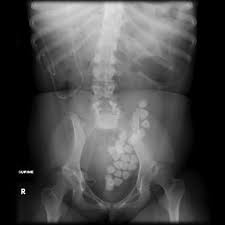

The stones will usually show up white on the x ray.

Kidney stones dog x ray. Kidney stones are a serious medical condition that requires prompt medical treatment. Once your dog has been diagnosed with kidney stones it will be your responsibility to control the condition long term. If kidney stones are suspected your vet will take x rays.

Overview stones of the urinary tract begin as microscopic crystals that aggregate to form stones of variable size and shape anywhere within the urinary system including the kidneys ureters and urethra although stones of the urinary bladder are most common. Cystine stones excessive elimination of cystine in the urine is an inherited disorder of kidney tubular transport that is thought to be the primary cause of cystine stones figure 5. Follow up appointments for urinalysis and or abdominal x rays should be done every 4 6 weeks after treatment initiation to ensure stones are dissolving and new ones are not forming.

These techniques are helpful to provide the outline of the stones in your dog s kidney. Kidney stones in dogs happen when crystals or stones form in the kidneys usually due to an abnormal concentration of mineral salts in the urine. Dogs with small kidney stones really may show no signs at all.

Herbal treatment at dr. A pica case confused with renal and bladder stones source. These images can be fetched after conducting tests using abdominal x ray contrast radiography or ultrasound equipment.

Canine kidney stones diagnosis. Kidney stones may show up on x rays of the belly that are being taken for unrelated reasons as a so called incidental finding for instance they may be discovered when you think your pooch may have eaten something he shouldn t have like one of your favorite earrings. There are several types of bladder stones.